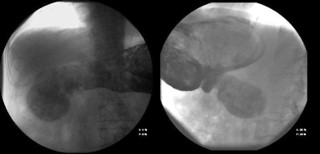

Computed Tomography (CT) scan performed at the time of admission revealed abundant food content with organized appearance in the abdomen (Figure 1), which was morphologically similar to that observed in previous CT scans. The findings supported chronic food retention with difficulty in gastric emptying at the level of pyloric antrum. Pharyngo-esophageal study revealed the presence of a bezoar occupying the entire gastric chamber with normal esophageal motility (Figure 2).

Figure 2: Pharyngo-esophageal study.